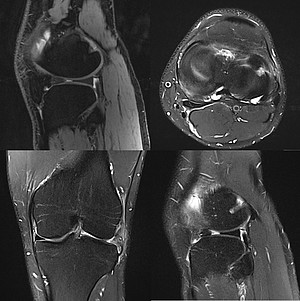

• MRT Bildgebung von Gelenken im Rahmen degenerativer, entzündlicher und traumatischer Veränderungen

Außer der regulären Patientenversorgung bieten wir Leistungs- und Profisportlern unsere sofortige und vollumfängliche radiologische Betreuung bei Sportverletzungen an. Ziel dabei ist die schnellstmögliche Diagnosestellung, die Grundlage für eine optimale Therapie ist. So soll zum einen die möglichst zeitnahe Rückkehr zu Training und Wettkampf ermöglicht, zum anderen eine verfrühte Wiederaufnahme der Belastung verhindert werden, die zu einer Verschleppung der Verletzung und/oder Folgeverletzungen führen könnte. Sportverletzungen können den gesamten Bewegungsapparat betreffen, besonders häufig sind Verletzungen von Sprunggelenk, Knie, Schulter und Ellenbogen. Allerdings kommen unter Sportlern auch Verletzungen gehäuft vor, die in der Gesamtbevölkerung eher selten sind, wie z.B. Abrisse von Muskeln oder Verletzungen des Muskel-Sehnen-Übergangs. So kann beispielsweise die Verletzung eines schmächtigen Bandzügels eine derartige Gelenkinstabilität bewirken, dass eine Belastung auf Wettkampfniveau unmöglich wird.